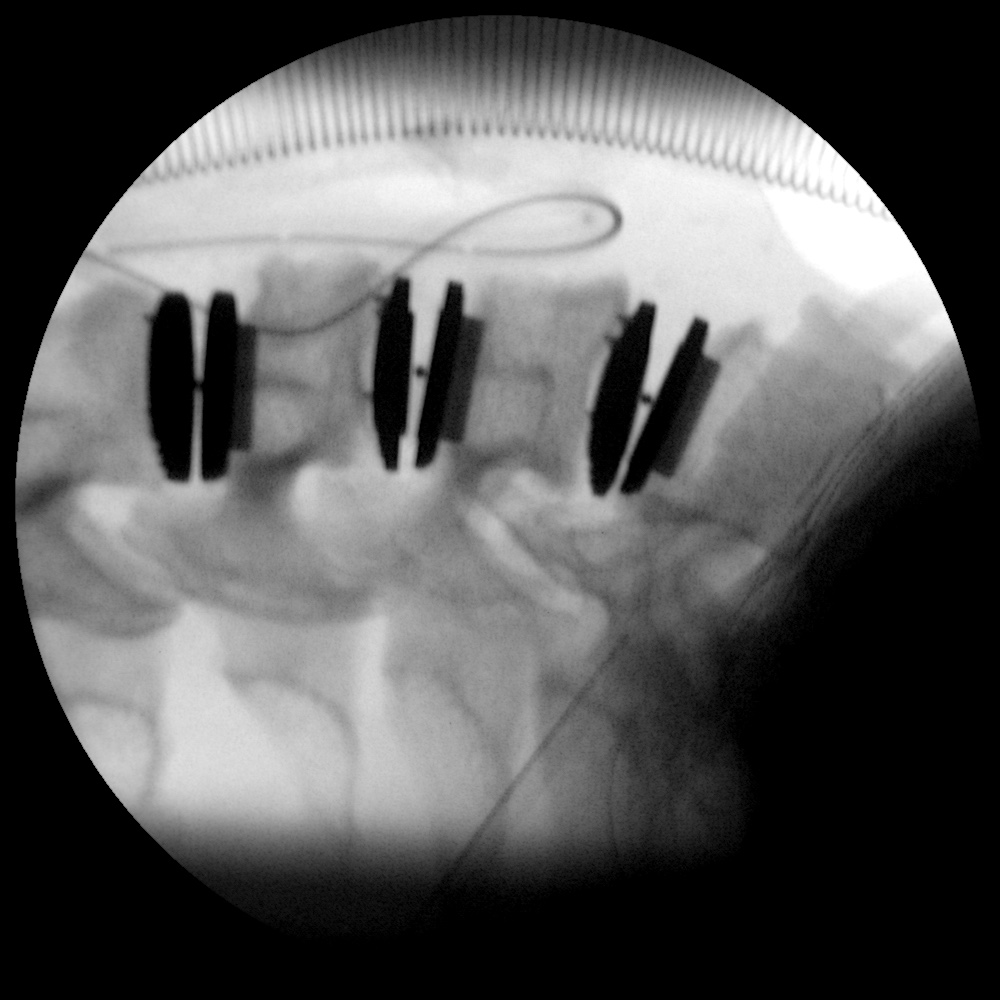

Caso clínico: endoscopia de columna multinivel L4L5 y L5S1

Durante la intervención quirúrgica, se abordarán los dos niveles mediante la técnica de endoscopia de columna.